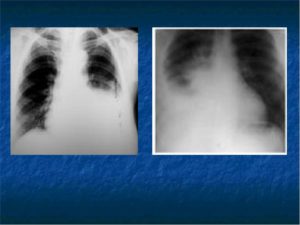

На рентгенограмме выпот представляет собой однородное интенсивное затемнение с косой верхней границей, которая идет книзу и кнутри. При этом отмечается смещение органов средостения в здоровую сторону.

Диагноз экссудативного плеврита подтверждается данными рентгенографии или рентгеноскопии легких, позволяющих выявить интенсивное гомогенное затемнение, смещение сердца в здоровую сторону. Для предварительного определения количества выпота целесообразно проведение УЗИ плевральной полости.

Стрелкой на изображении указан экссудат.

Рентгенограмма, светлая область – местонахождение экссудата.

По рентгенограмме можно определить наличие выпота и его примерный уровень, то есть получить примерное представление о количестве экссудата.